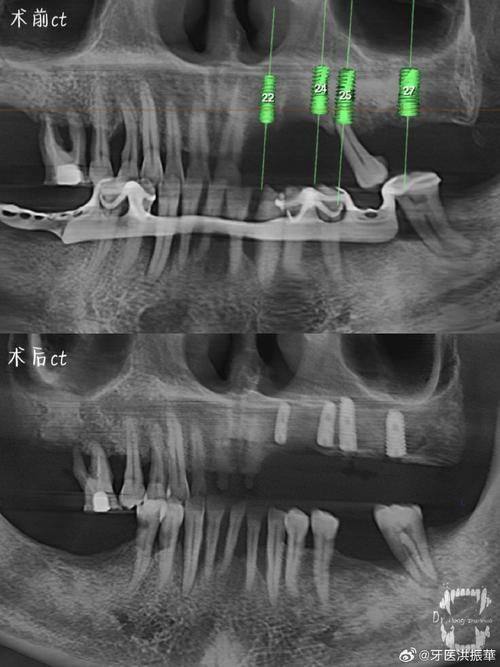

口腔种植:作为省内技术领跑的种植中 心,可开展常规种植、骨量不足情况下的植骨手术、即拔即种、即刻修复等各类复杂种植技术,技术规模处于行业领跑地位